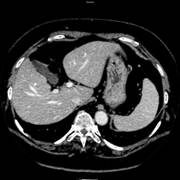

スペクトラルCTイメージングはX 線による物質固有のX線減弱係数を利用し、異なるエネルギー値をそれぞれ透過させた際の差を利用することにより、対象領域の素材密度、組織の特性をイメージングすることができます。GE製MDCT Discovery CT750 HD に搭載されている“Gemstone Spectral Imaging(GSI)” は、初めてスペクトラルCTイメージングを臨床で使用可能にした機能です。

さらにその結果として、逆に物質のX線減弱係数に比例した加重加算を行うことにより、ビームハードニングの影響を取り除いた正確なCT値を有する画像を作成することができます。

スペクトラルCTイメージングを行う際には2つの異なるエネルギー、低エネルギーと高エネルギーでの撮影データが必要となります。また、データを収集する際には2つのデータ間にエネルギー以外の差異、すなわち位置ずれやタイミングのずれがないことが大前提となります。さらには、ビームハードニングアーチファクトの補正が間違いなく出来ていることも非常に重要な要素となります。